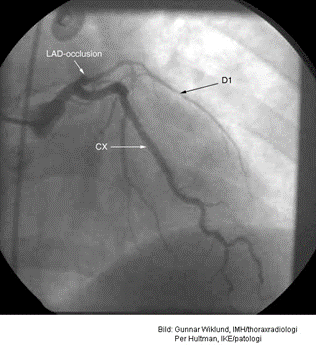

Vad ser du här och vad kan göras åt detta?

Proximal ocklusion i vänstra främre nedåtgående koronarkärlet (left anterior descending coronary artery, LAD). Högerkärlet visar flera smärre förändringar men inga signifikanta stenoser.

PCI kan genomföras (ballongsprängning) och ett stent kan läggas in i proximala LAD